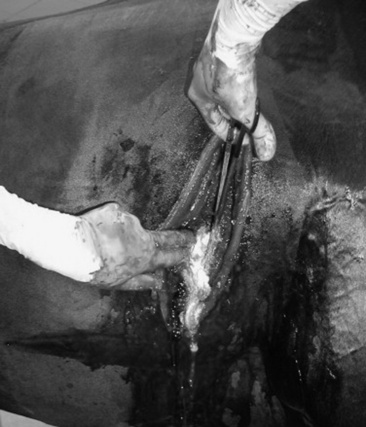

Thoracocentesis

Aspiration from the pleural space is a simple, easily performed, inexpensive procedure that can be both diagnostic and therapeutic. In the horse with septic or neoplastic effusions, sedation is often unnecessary because the procedure causes only minimal additional discomfort. After ultrasonographic evaluation of the thorax, a point is chosen at which drainage or fluid sampling would seem most appropriate—frequently in the sixth or seventh intercostal space 10 cm dorsal to the olecranon and above the lateral thoracic vein. The area should be clipped, if it was not clipped for the thoracic ultrasound examination, and surgically prepared. Multiple sites may be needed in horses with loculated pockets of fluid in the pleural cavity, and these sites should also be chosen using ultrasonography. The skin and intercostal tissue down to the pleura are anesthetized with lidocaine, and a stab incision is made. A sterile 2- to 3-inch teat cannula or bitch catheter is introduced immediately cranial to the rib border to avoid the intercostal nerve and vessel along the caudal aspect of the ribs. The cannula should be attached to sterile intravenous (IV) extension tubing and a three-way stopcock. When the cannula is advanced bluntly through the parietal pleura, a sudden loss of the force required to advance is felt. Aspiration should be attempted at this point. The orientation of the cannula can be varied to reach as much fluid as possible. Normally only a few milliliters of straw-colored fluid are obtained. In cases of pleural effusion, as much as 30 L may be removed from each side of the chest (Fig. 31-3). If fluid is excessive, the tubing can be extended over a bucket for gravity drainage, or a vacuum pump with fluid trap can be attached. Once the procedure is complete, a purse-string suture is placed around the stab incision, and the cannula is withdrawn while the suture is tightened. In cases in which the effusion is large and expected to continue forming for several days, the initial drainage can be performed by placing a chest tube instead of puncturing the pleural space with a teat cannula. If a chest tube is to be left in place it should be secured with a Chinese finger trap suture and the end covered by a Heimlich valve to prevent aspiration of air into the thorax through the tube. If the thorax is being drained rapidly, the patient should be watched carefully for signs of distress, as draining of large volumes can alter cardiovascular parameters significantly.